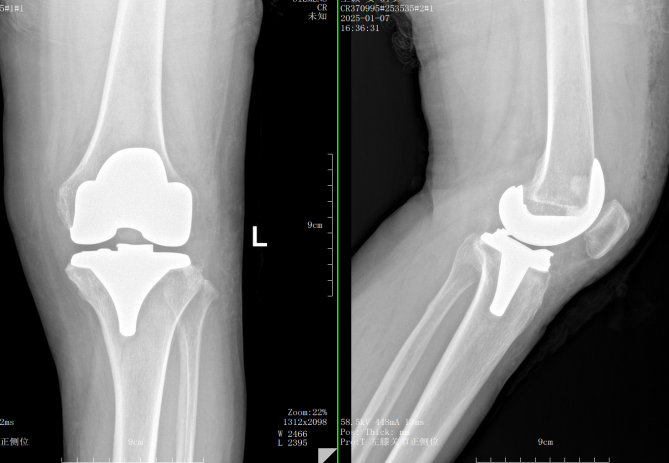

手术前,全华山主任关节置换团队为王阿姨进行了全面而细致的知情告知,耐心解答了患者的疑问,确保患者在术前做好充足的心理准备。在手术过程中,关节置换团队依托丰富的临床经验和先进的手术技术,成功地为王阿姨更换了损坏的膝关节,并尽可能减少了对周围组织的损伤,缩短了术后恢复时间。

术后 术前

术后,医护团队立即展开了精细的护理,并制定了康复方案。为了帮助患者早日恢复,医护人员逐步引导王阿姨进行关节功能锻炼,同时密切关注术后的疼痛管理和感染预防。通过共同努力,王阿姨在术后恢复过程中表现出色,功能逐渐得到改善,疼痛逐日减轻。住院时间仅一周,各项指标恢复良好,目前已出院居家康复。